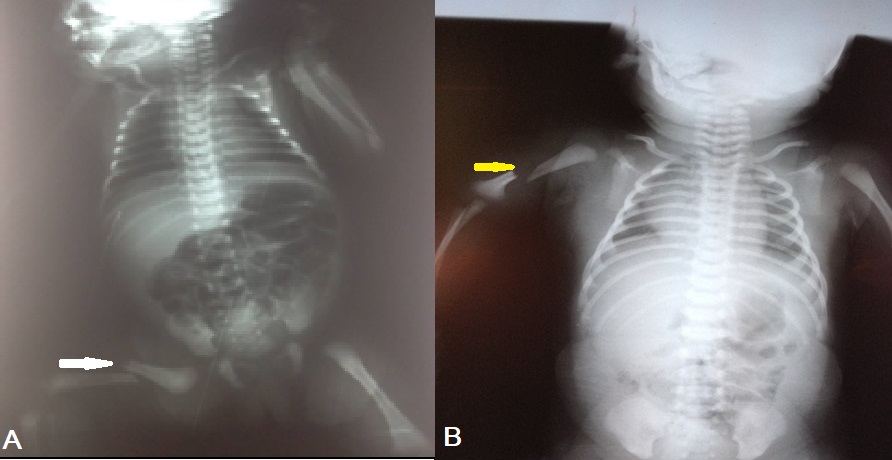

Skeleton trauma: A male term newborn weighing 3.8kg born by C-section due to failure of progression of the delivery. There were no reported difficulties in delivering the baby who cried immediately at birth with an Apgar score of 9. A few hours later, the baby developed irritability and inconsolable cry along with swelling of the right lower limb. Radiographic examination revealed a diaphyseal fracture of the right femur (Fig. 2A) . Immobilization of the limb with a bandage for 3 weeks was done and the baby discharged home. The follow-up showed a good outcome.

Another male newborn with the gestational age of 40 weeks, cephalic presentation, weighing 4 kg, was born by spontaneous vaginal delivery. This fetal macrosomia was complicated with brachial plexus injury, probably due to traction of the neck at birth. Radiographs of the shoulder and upper arm showed a fracture of the right humerus(Fig. 2B). Both lesions were managed in our department immediately by immobilization by calf strip for 4 weeks, and the limb was held to the body by a scarf. One month later, rehabilitation was started. A good functional outcome was obtained after 6 months.

The bony injury is rare; the clavicular fracture is the most common bony injury which has already been reported. However, there are few reports of long bone fractures that occurred during C-section delivery. In principle, a C-section is supposed to prevent long bone fractures, but this kind of complication cannot be inevitable. The first case of femur fracture in a newborn was described in 1922 by Ehrenfest.[11] A study from Israel showed that 12 femur fractures occurred in C-section versus 5 fractures during vaginal delivery.[12] Other fractures are occasionally reported such as fractures of the tibia, radius, and rarely the humerus. Fracture of the humerus in a neonate born by C-section is extremely infrequent. John et al. reported a case of humerus fracture during the C-section, which is quite rare.[13] However, the fracture of the humerus can be concomitant with the brachial plexus injuries as encountered in one of our patients with skeleton injuries.[14], [15] Dolivet et al. identified ten newborns with at least one fracture out of 7930 C-sections (1.26%); in two cases of these ten, there was a fracture of the humerus.[3] The femur fractures are usually caused by undue traction, poor delivery technique, small uterine incision, and inadequate relaxation especially in case of fetal macrosomia. Furthermore, these injuries can also happen when the breech is well engaged in the pelvis or when a footling has descended into the vagina.[16]

A) Femur fracture (white arrow) in the first case with skeleton injury. B) Humerus fracture (yellow arrow) in the second case of skeleton injury.